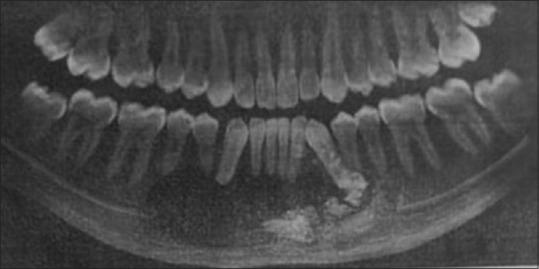

Calcifying odontogenic cyst (COC) or Gorlin's cyst categorized as a distinct entity by Gorlin . in 1962. It is a rare benign developmental cystic lesion that accounts for less than 1% of all odontogenic cysts. It can occur in association with various types of odontogenic tumors such as odontomas. COC is a hybrid lesion of the jaw presenting a manifold variety of clinical behaviors and histopathological characteristics including cystic, solid (neoplastic), and aggressive forms. COC exhibits diversity in terms of its clinical presentations, histopathologic features, and biological behavior. Normally, it presents as asymptomatic, slow developing lesion affecting the maxilla and mandible equally with strong predilection for the anterior segment. Radiographically, these lesions usually present as a unilocular, well-defined radiolucency with radiopaque structures within the lesion, either as irregular calcifications or tooth-like densities. The distinct features of COC as solid or cystic lesions presents with an ameloblastomous component admixed with varying proportions of ghost cells and spherical calcifications. Here, we report an article of calcifying odontogenic cyst associated with compound odontoma in a young patient with lesion in the anterior mandible with review of the various terminologies and classification and histopathology.

钙化性牙源性囊肿(COC)或戈林囊肿由戈林于1962年归类为一种独特的实体。它是一种罕见的良性发育性囊性病变,占所有牙源性囊肿的比例不到1%。它可与各种类型的牙源性肿瘤如牙瘤相关联。COC是颌骨的一种混合性病变,表现出多种临床行为和组织病理学特征,包括囊性、实性(肿瘤性)和侵袭性形式。COC在临床表现、组织病理学特征和生物学行为方面表现出多样性。通常,它表现为无症状、发展缓慢的病变,对上颌骨和下颌骨的影响相同,以前段为强烈偏好部位。在影像学上,这些病变通常表现为单房、边界清晰的透射区,病变内有不透射线的结构,表现为不规则钙化或牙样密度。COC作为实性或囊性病变的独特特征表现为成釉细胞瘤成分与不同比例的影细胞和球形钙化混合。在此,我们报告一篇关于一名年轻患者下颌前部病变中钙化性牙源性囊肿与复合性牙瘤相关的文章,并对各种术语、分类和组织病理学进行综述。